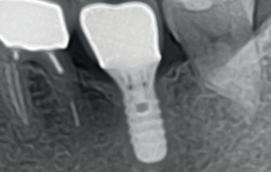

Na vier maanden wordt er een CBCT gemaakt om het botvolume te kunnen beoordelen en een digitale planning te kunnen maken voor het plaatsen van het implantaat. Tevens wordt de stabiliteit van de botpieken op het buurelementen bekeken (foto 15 en 16).

Tijdens het verwijderen van het membraan is het botvolume klinisch waarneembaar en blijkt dat er voldoende bot is om het implantaat te kunnen plaat-

sen. Tijdens deze procedure wordt er ook een free gingival graft van het palatum gehaald. Deze wordt buccaal aangebracht van de 22 en 23 om zo de recessie zoveel mogelijk te bedekken en de papil tussen de 22 en 23 van meer volume te voorzien.

De flap en graft worden met poly-propelene 6.0 hechtingen gefixeerd. De tijdelijke reconstructie wordt herplaatst (foto 17-20).

In afbeeldingen 5a-d is de implantaatkroon 37 te zien, twee jaar na plaatsing. Op de röntgenfoto is herstel van zowel corticaal als spongieus bot te zien. (De CB-CT was vervaardigd in verband met implantologische indicatie in het naastliggende gebied).